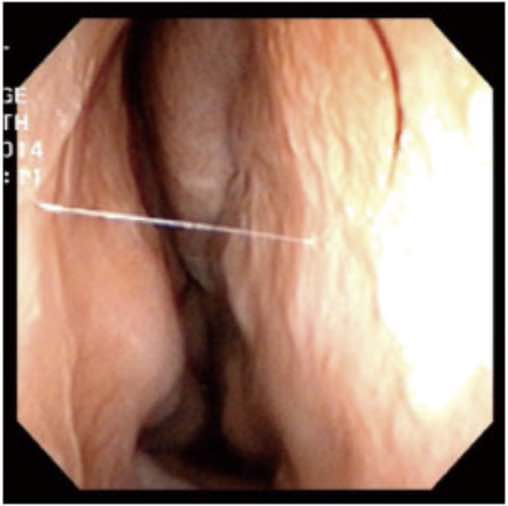

▲透過手術前後鼻阻力圖對照,術前右側鼻阻力線都接近水平線,表示呼吸阻力極大,術後鼻阻力線恢復正常曲線,接近兩邊對稱,表示呼吸恢復暢通,傷口也恢復良好。